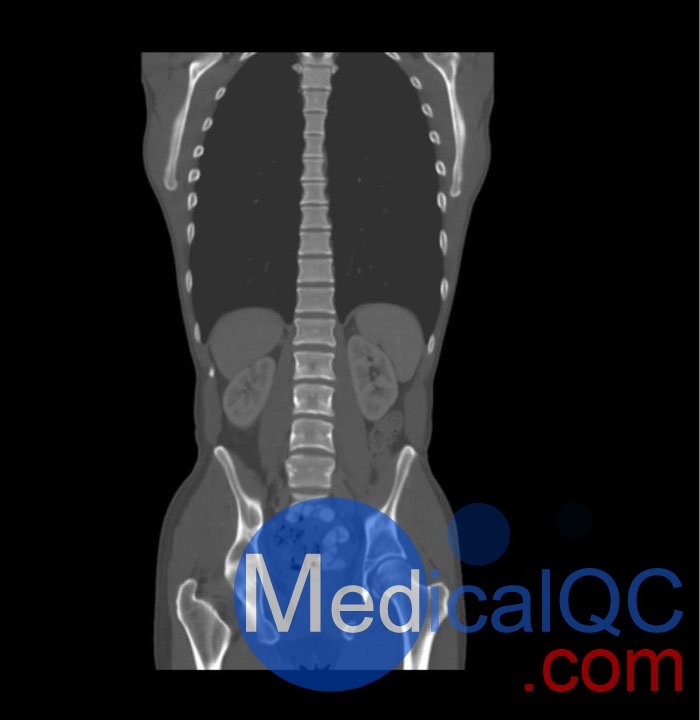

WEK57-01門靜脈期軀干模體,WEK57-01軀干模型模擬了門靜脈期的造影劑增強(qiáng)胸部、腹部和骨盆。它覆蓋了會陰的第二胸椎。

右側(cè)有髂淋巴結(jié)腫塊。

該模型可用于 CT(包括 CBCT)以評估和優(yōu)化成像性能和后處理應(yīng)用,包括支持 AI 的應(yīng)用。它也適用于培訓(xùn)目的。

該模型提供了對軟組織和骨組織的詳細(xì)而逼真的模擬。包括肺在內(nèi)的空隙充滿了大約 -160HU的纖維素聚合物復(fù)合材料。

真實模擬脈管系統(tǒng)、骨骼和軟組織,包括肺、心臟、肝臟、膽囊、胰腺、脾臟、腎上腺、腎臟、胃、小腸、結(jié)腸、膀胱和前列腺。

右側(cè)髂外淋巴結(jié)腫塊。

WEK57-01門靜脈期軀干模體,WEK57-01軀干模型成像效果圖: